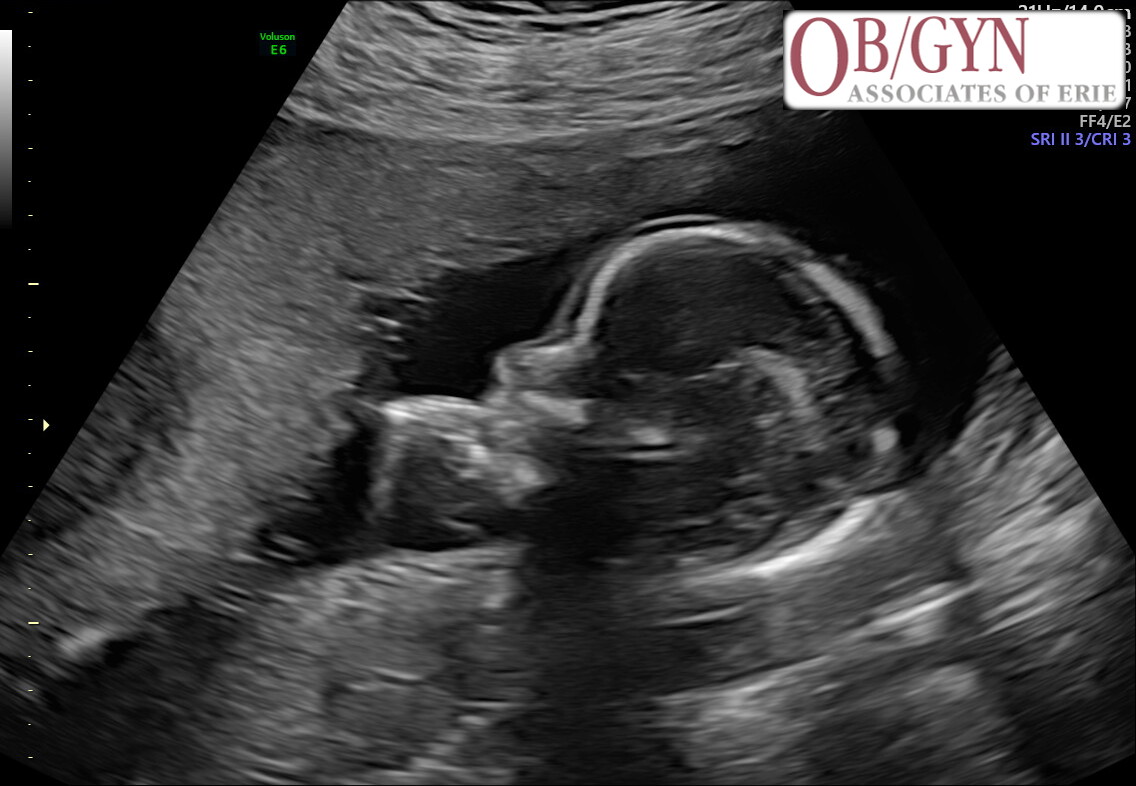

Awaiting the arrival of

Baby LaVette